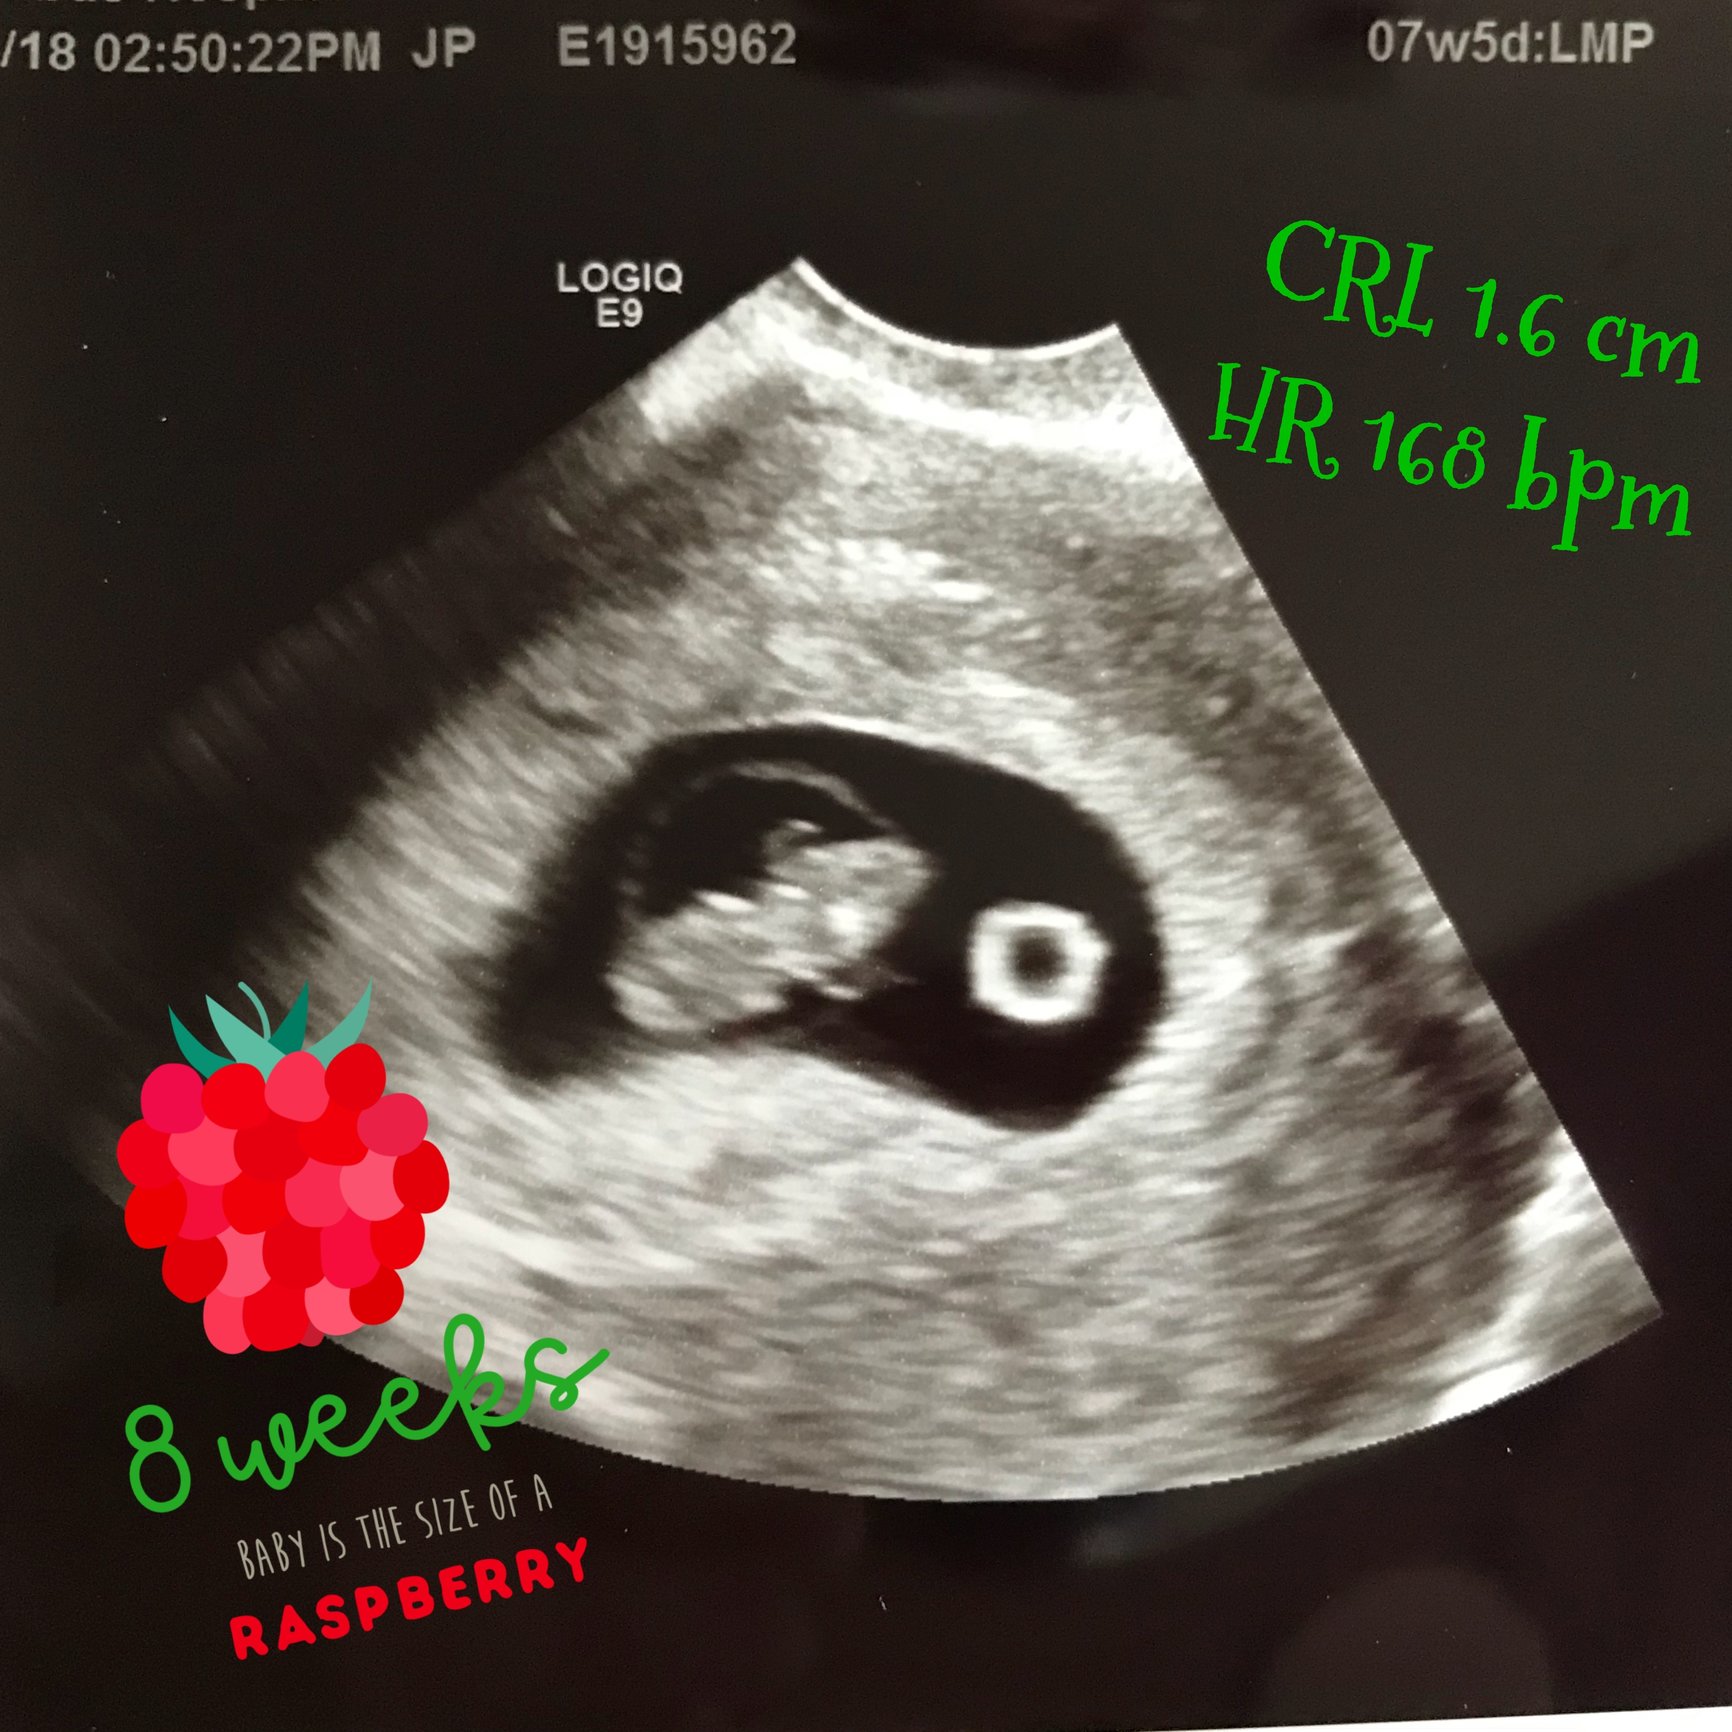

Hi everyone, 6 weeks ultrasound. I’m scheduled back for an 8 weeks ultrasound. Doctor said it’s twins but one is smaller than the other one that we had to wait and see if the other progresses. Has anyone had a similar situation? This is my 3rd pregnancy but first time twins.